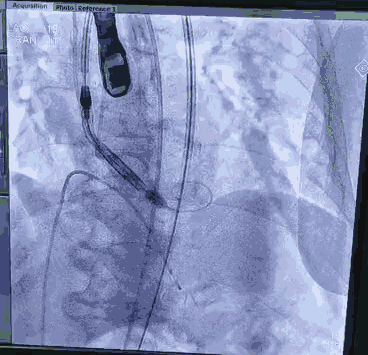

顺利跨瓣,测得跨瓣压差62mmHg。送20mm球囊扩张主动脉瓣,经右桡动脉猪尾导管造影,冠脉切线位未见右冠脉显影。为策安全,决定对RCA行冠脉保护,送JR4导管及guidzila和3.5球囊行冠脉保护。置入24mm微创 vitaflow瓣膜标准位释放。复查造影显示少量主动脉瓣返流,左右冠显示良好,撤除右冠保护。术后测压差为10mmHg。缝合双侧股动脉。术后恢复良好,次日转回普通病房,顺利出院。